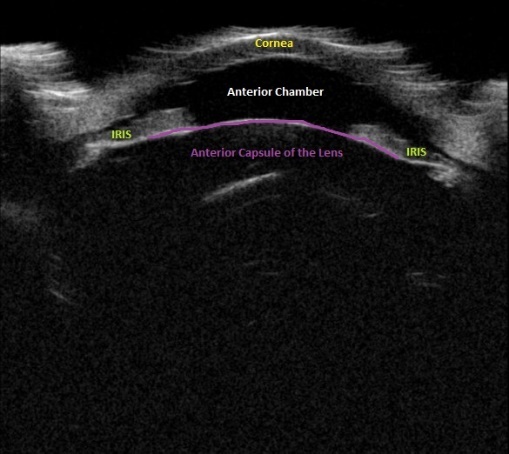

Upon initial evaluation, the patient presented with stable vital signs. His IOP (normal range 10-21 mmHg) was found to be 54 in the right eye, 56 in the left eye. The patient received acetazolamide 250 mg IV and ophthalmology was consulted. Upon evaluation by ophthalmology, the IOP was 34 and 28. The patient was previously emmetropic, but reported persistent blurred vision, and had a manifest refraction of – 3.00 diopters in both eyes in the ED. Visual acuity was assessed with a near card without correction, and found to be 20/25 in the right eye, 20/25 in the left eye. Gonioscopy showed a closed angle in both eyes that could be opened with indentation. There was trace chemosis in the conjunctiva in both eyes, with shallow anterior chambers (Figure 1), and minimal inflammatory cells. The optic nerves appeared perfused, and there were shallow choroidal folds present in the macula. It was felt that his presentation was due to bilateral ciliary body effusion (Figure 2 & 3) causing anterior displacement of the lens-iris diaphragm, closing the angle and leading to this myopic shift.